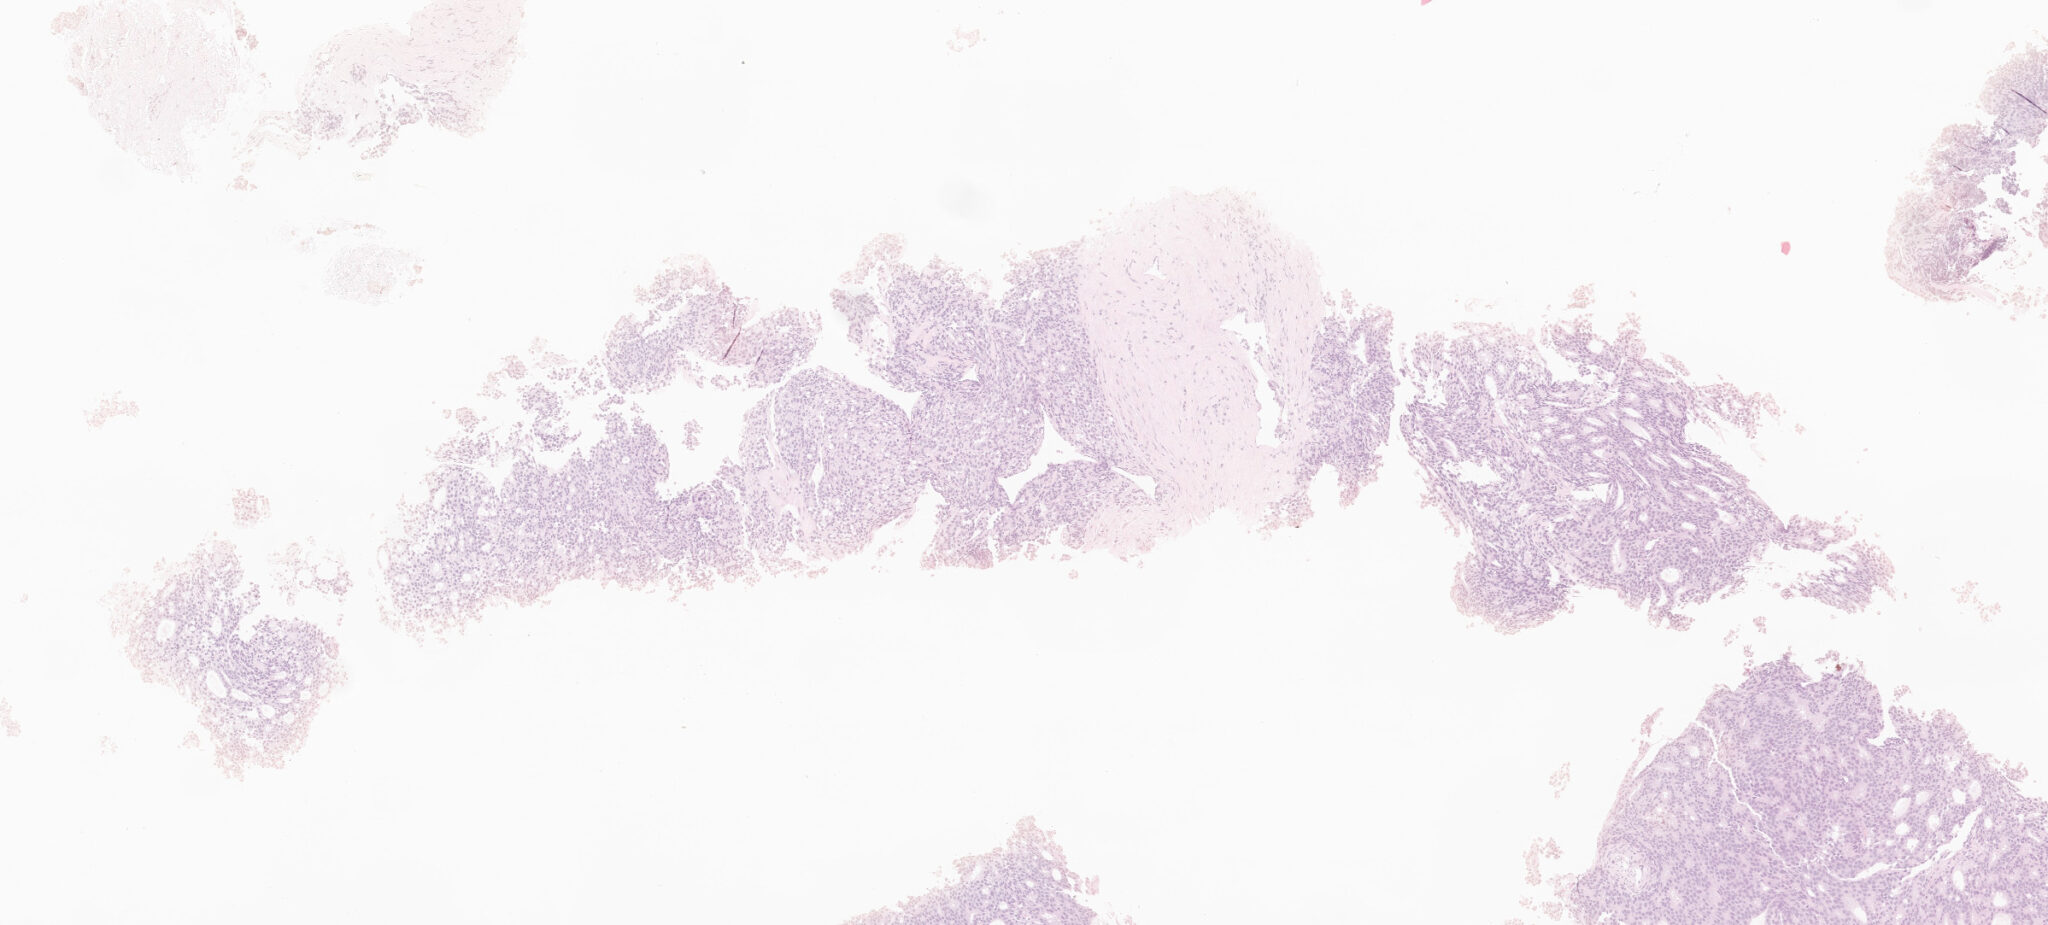

Il vetrino fisico viene digitalizzato con l’utilizzo di appositi digitalizzatori.

Gli algoritmi brevettati da AEQUIP riducono la variabilità cromatica ed ottimizzano l’immagine digitalizzata.

Gli algoritmi proprietari di AEQUIP riescono ad estrarre parametri quantitativi specifici rispetto alla patologia ed al tessuto contenuto nel vetrino digitalizzato.